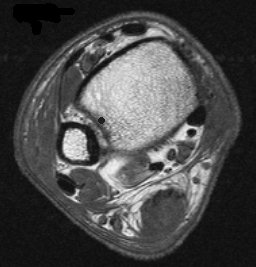

12251.jpg (12881 bytes) 12287.jpg (14606 bytes)

History

Description

Diagnosis